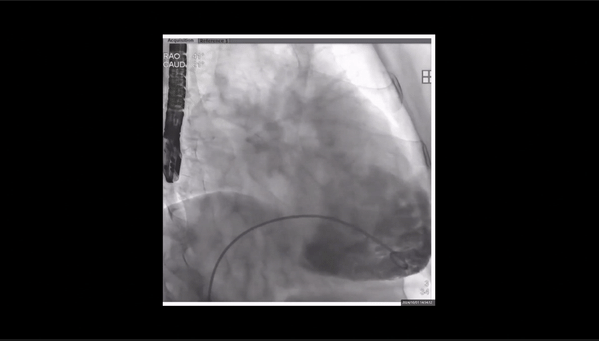

術前右室造影

夾持件位置確認

室間隔位置確認